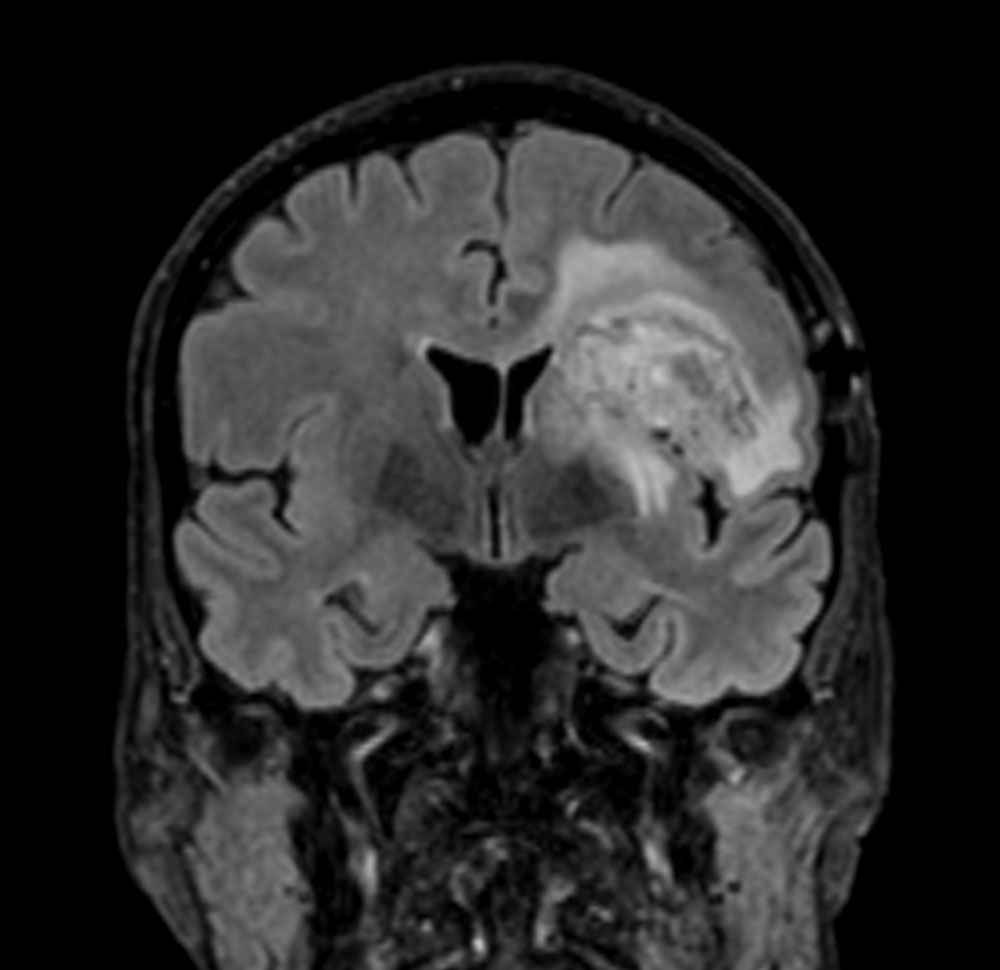

3D BrainVIEW FLAIR (coronal reformat)